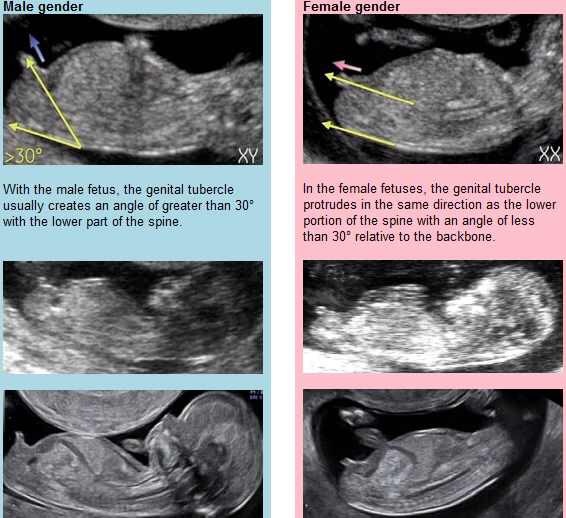

The little sticky up part on the end (if I'm right that is!) attached photo explains the nub theory Smilexxx